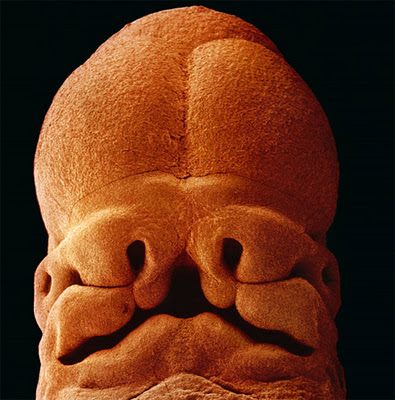

5 շաբաթական սաղմ: Երկարությունը մոտ 9մմ է: Սկսում է ձևավորվել դեմքը, ի հայտ են գալիս բերանի, քթի և աչքերի բացվածքները:

4 շաբաթական սաղմ

6 շաբաթական սաղմ

7 շաբաթական սաղմ

8 շաբաթական սաղմ: Արագ զարգացող պտուղը պաշտպանված է պտղապարկով: